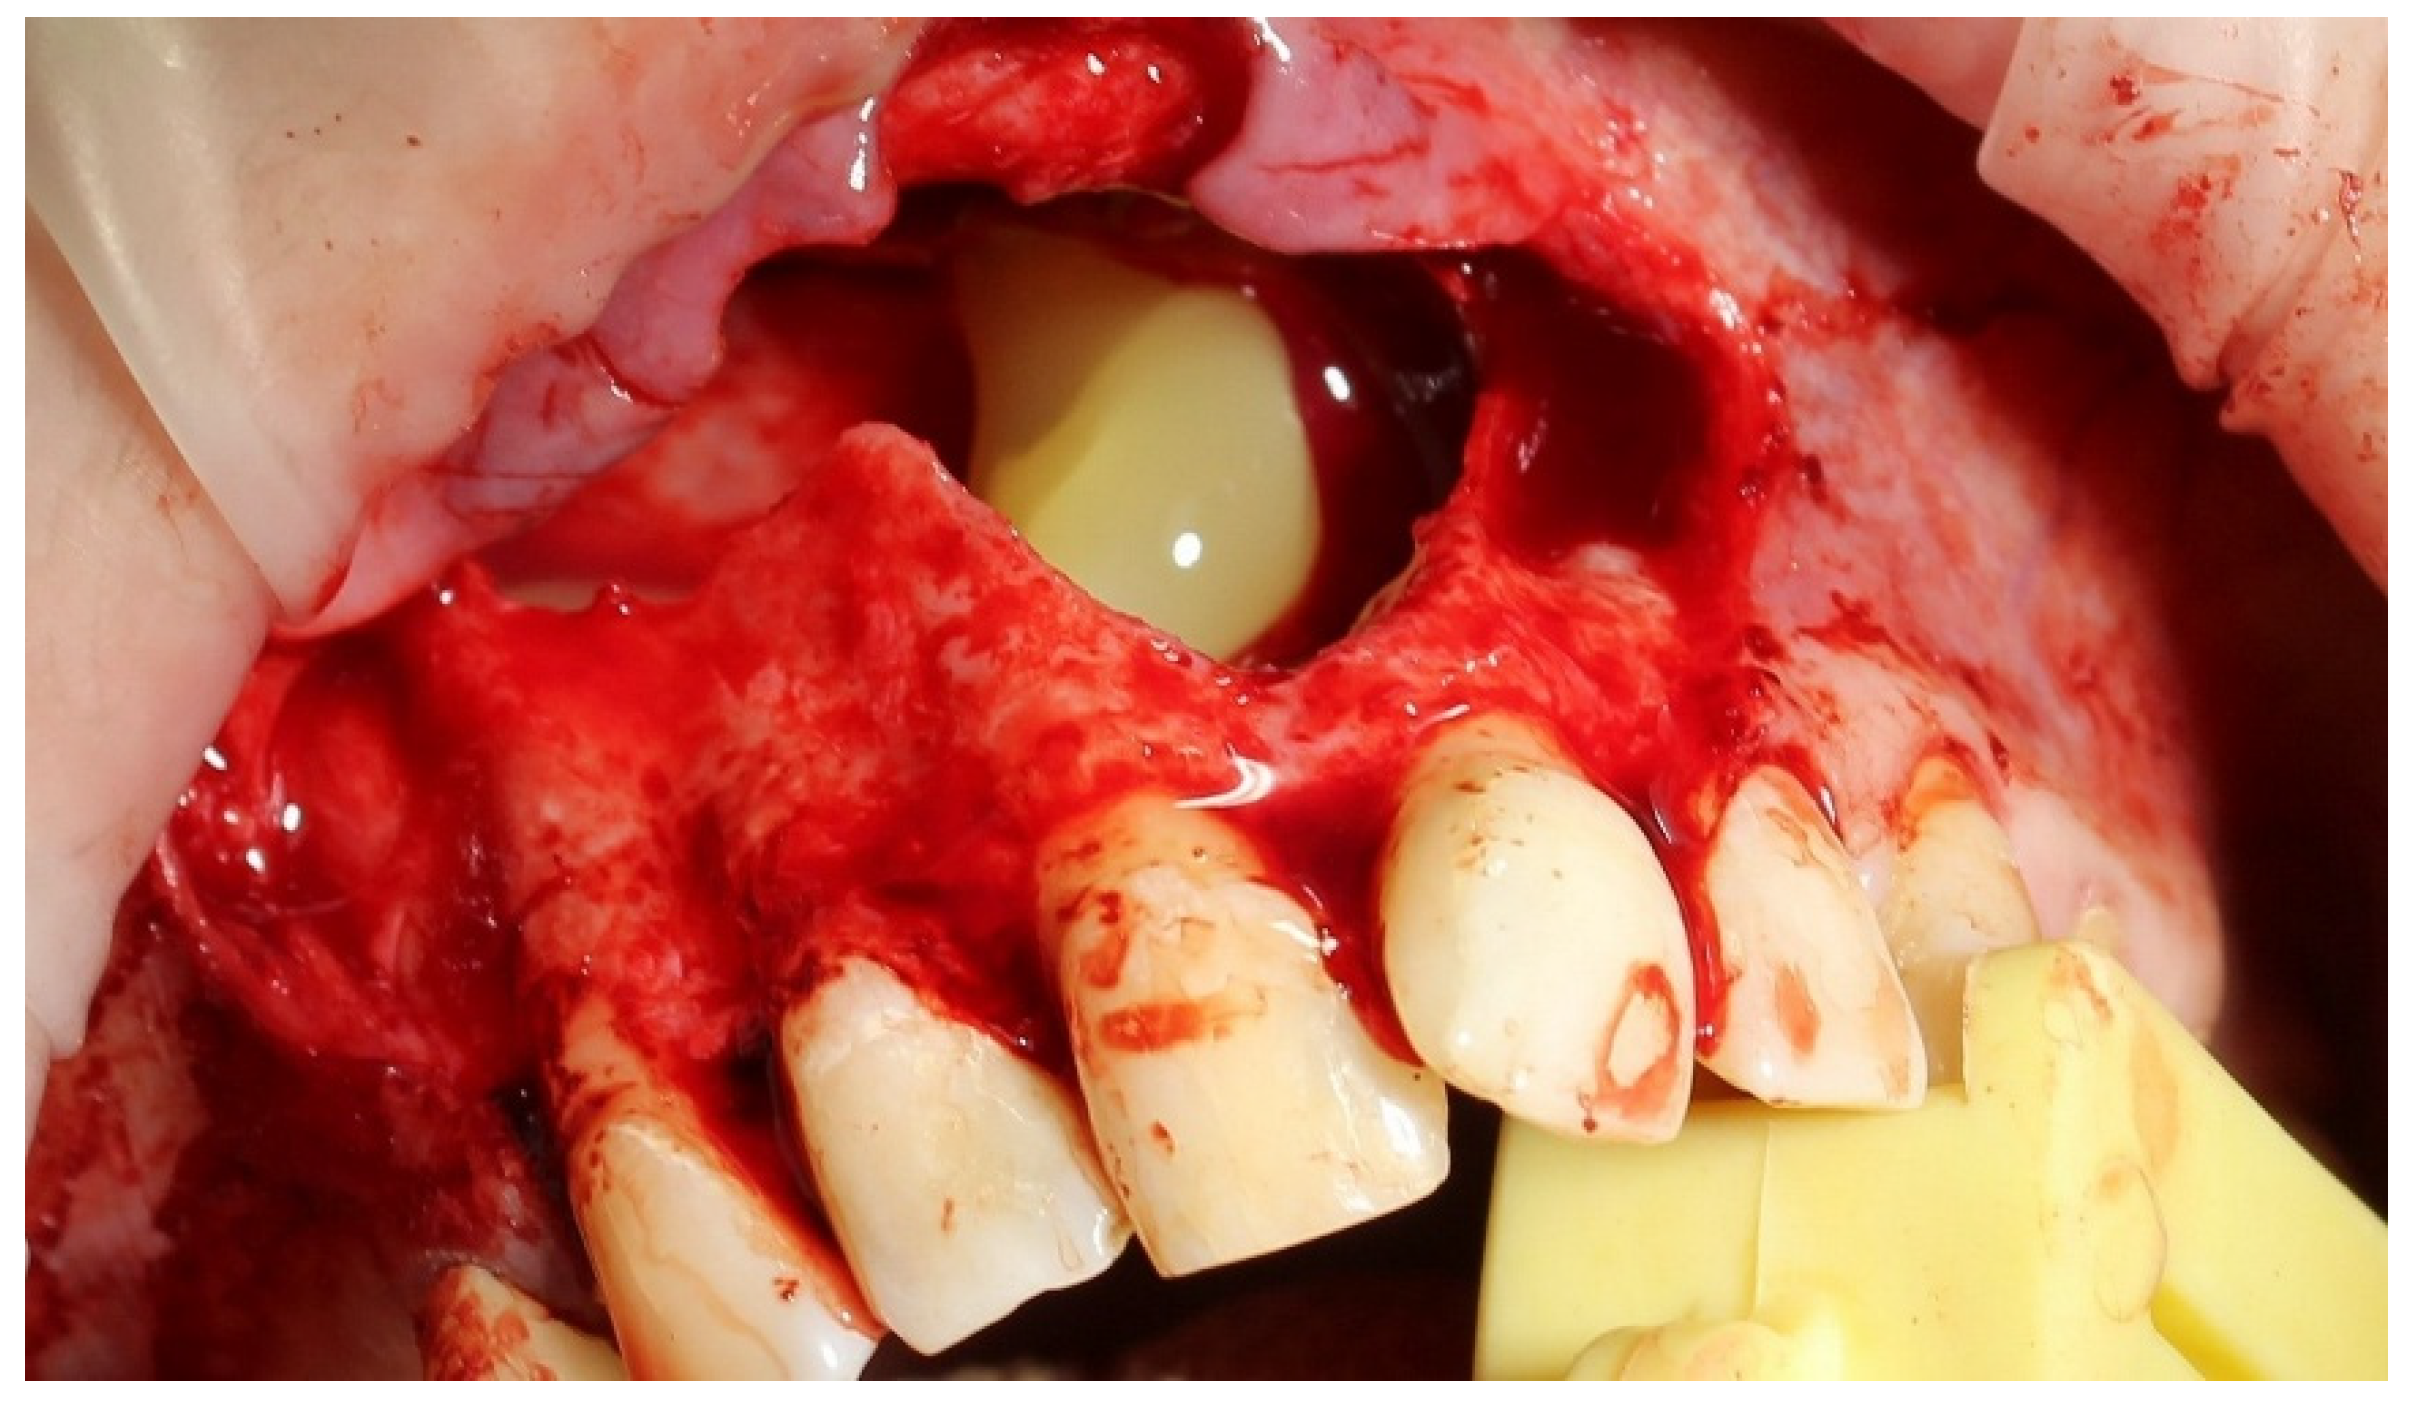

For one month, the patient received complex conservative therapy to relieve acute inflammation. Before surgery, the cyst-related teeth 1.3, 1.2, 1.1 and 2.1 were endodontically treated. Cyst enucleation was performed with preliminary sedation under local anesthesia. Following the enucleation, histopathological analysis confirmed the presence of a radicular cyst. The apices of the teeth roots 1.3, 1.2, 1.1 and 2.1 protruding into the periradicular lesion were resected, the residual bone cavity was filled with PRF clot (Figure 2), and the bone wound was completely covered with a mucoperiosteal flap (Figure 3).

Figure 2. Bone cavity filled with platelet-rich fibrin clot.

Figure 3. Bone wound is completely covered with a mucoperiosteal flap.